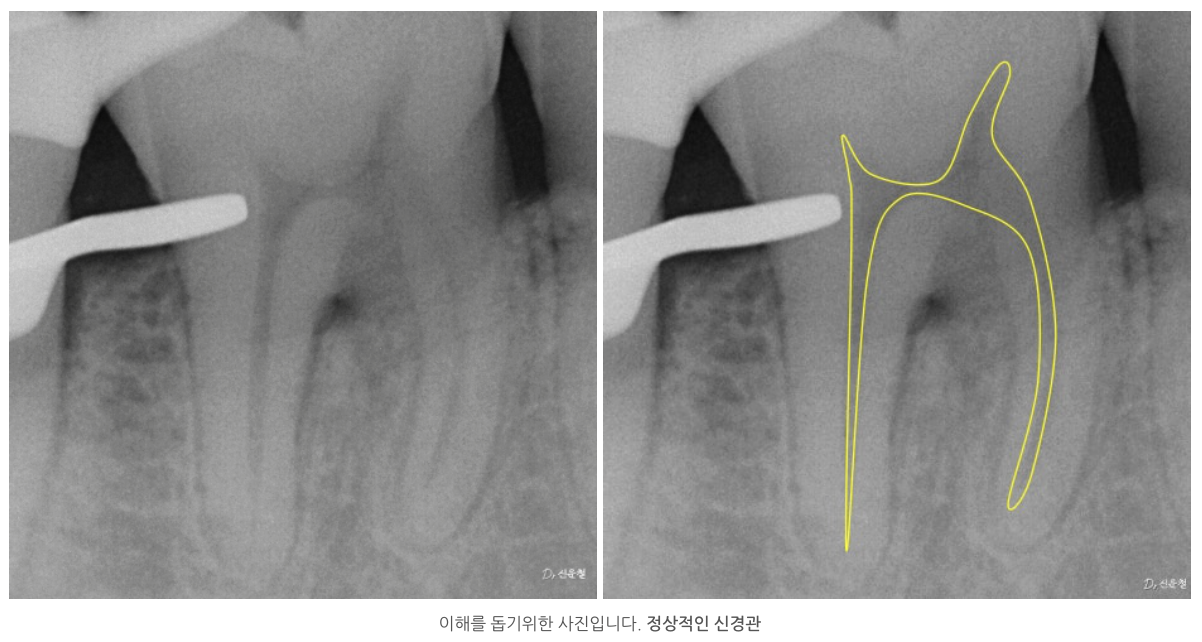

석회화란

원래 신경이 지나가야 할 공간이

시간이 지나면서 막히는 현상입니다.

방사선 사진에서 신경관이 잘 보이지 않거나

CT에서 신경이 있어야 할 자리가

빈 공간이 아닌 뼈처럼 보이는 경우가 이에 해당합니다.

겉으로 보면

“이제는 방법이 없는 치아”처럼 보일 수 있습니다.